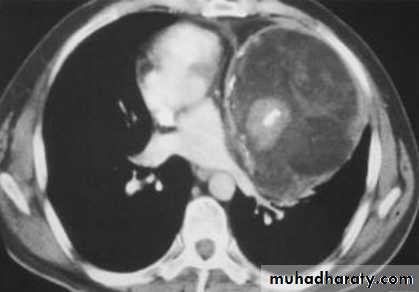

Aortic aneurysm

Aortic dissection